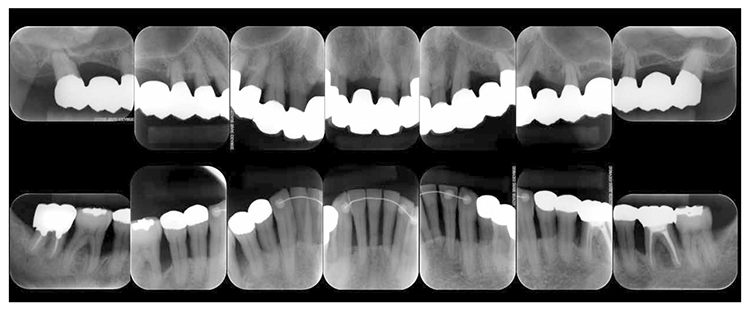

2) Reevaluation testing (February 2010)

At reevaluation testing after basic periodontal treatment, the color of gingiva improved to pink, and findings showed that inflammation in the marginal gingiva with primarily blood congestion had subsided. Class 4 gingival recession (Miller’s gingival recession classification) was observed on the entire jaw. (Fig.3a). The average PD of the entire jaw was 2.8mm, maximum PD was 10.0mm, the ratio of PD of 3mm or below was 84.0%, PD of 4-6mm was 12.5%, PD of 7mm or above was 3.5% and BOP rate improved to 11.8%. However, PD of 7mm remained on 17, 10.0mm on 27, 5.0mm on 36, and 7.0mm on 46. Additionally grade 1 furcation involvement remained on the buckle and lingual side of 36, mesial distal direction on the buckle side of 17, grade 2 on the buckle side of 27. Teeth mobility was grade 1 on 44 and 46 (Fig.3b). X-ray findings showed that dental calculus was removed from the gingival margin on the maxilla and mandible. Despite the clearly visible alveolar hard line, no improvement was shown on the alveolar bone. (Fig.3c).

Fig 3a

(Fig.3a) Intraoral photo after completion of basic periodontal treatment has completed (2010.1)

Fig 3b

(Fig.3b) Reevaluation and examination after completion of basic periodontal treatment (January 2010)

Fig 3c

(Fig.3c) Dental X-ray 14 after completion of basic periodontal treatment (January 2010)